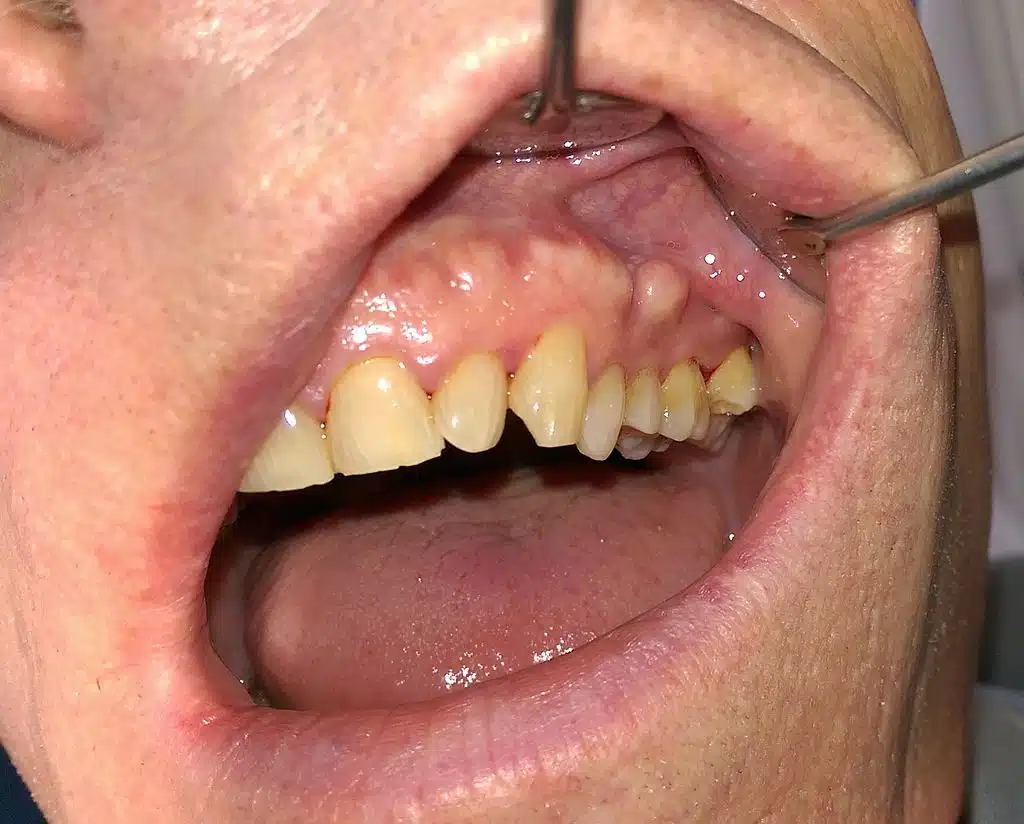

Why Tooth Loss Accelerates After Placement

When reduced oral care, a cariogenic (cavity-causing) diet, medication-induced dry mouth, and limited early intervention converge, tooth loss accelerates. Teeth that might have been saved with earlier attention are instead lost to infection, fracture, or pain.

Patients should not be getting sicker simply because they are now in a structured care environment—but too often, they are.

Oral health decline does not occur in isolation. Mouth pain reduces appetite. Difficulty chewing limits food choices. Tooth loss affects speech, appearance, and social interaction. Many residents become withdrawn, embarrassed, or depressed.

Depression then reduces motivation for self-care, including oral hygiene. The cycle reinforces itself, and the mouth becomes both a victim and a contributor to overall decline.